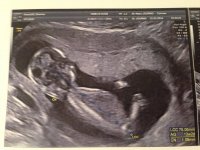

Bah disons qu elle doit assumer entièrement , moi je la guide c est tout , j ai déjà assez à faire avec mes soucis à moi surtut depuis la fermeture de mon AE , la grosse déprime .... Demain je l accompagne à l echo 3D car son cheri travaille ....

merci pour elle !! et en plus j avais raison sa gygy la premiere disait qu elle etait enceinte depuis le 25/10 .... et moi j avais recalculer ...c etait le 03/11 ... et bah paff j ai raison vu l echo elle a son terme le 03/08/2014.... une petite lionne pour accompagner sa tigresse de grand-mère ....

Pièces jointes

• babychouette.jpg

babychouette.jpg

117.4 KB · Affichages: 138